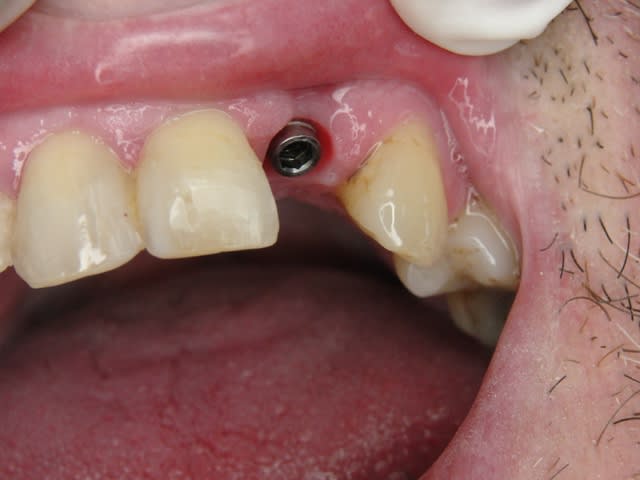

Photos d'un cas d'extraction implantation immédiate, stabilité primaire (de mémoire) assez élevée.. 60/70 N ..démontage du gingiva clips et du shuttle, pilier serré 40N, couronne procera

La pose de la couron nec'est faite 8 semaines apres l'extraction implantation immédiate, la particularité de ce systeme permet de ne pas démonter le shuttle ni la gingivaclip pour l'empreinte..je pense que ca aide bien à la qualité gingivale...radio controle ci jointe